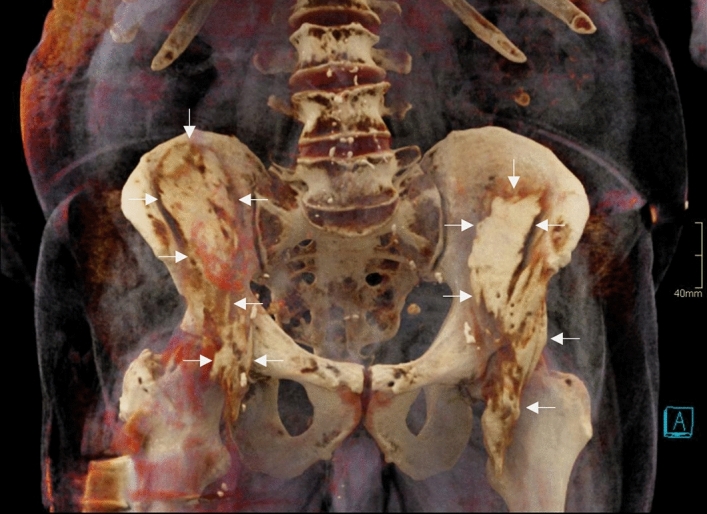

Figure 4.

A 3D volume rendered reconstruction of CT-imaging of a specimen that was randomized to receive bilateral S-FICB-H. Contrast reached a maximum height equal to the level of the fifth lumbar vertebra on the left side and the intervertebral disc of lumbar vertebrae four-five on the right side. The arrows point to the contrast.

The FN and LFCN were consistently involved in S-FICB-H, S-FICB and FNB, while these structures were considerably less often involved in I-FICB (22.2% and 44.4% of cases, respectively). Details of nerve involvement are summarized in Table 1. Figure 4 depicts a volume rendering reconstruction of a cadaver with typical injectate distribution patterns after bilateral S-FICB-H.